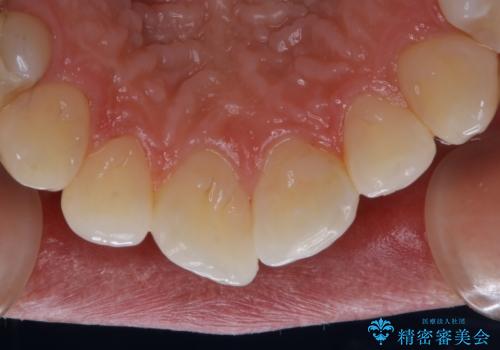

- 歯医者でのクリーニングはかなり久しぶりで、今後虫歯の治療もしていくので綺麗にしたいとのことでした。PMTC30分コースを行いました。

PMTCを行う際には担当の歯科衛生士が、患者様1人1人の虫歯・歯周病などのリスク・ブラッシングスキルなどを確認します。

単なる磨き方の指導だけではなく、歯並びや歯肉の状態、ライフスタイルなどにより、患者様に適した歯ブラシや歯磨剤の選択をしたり、お口のお悩みについてのご相談も承っております。